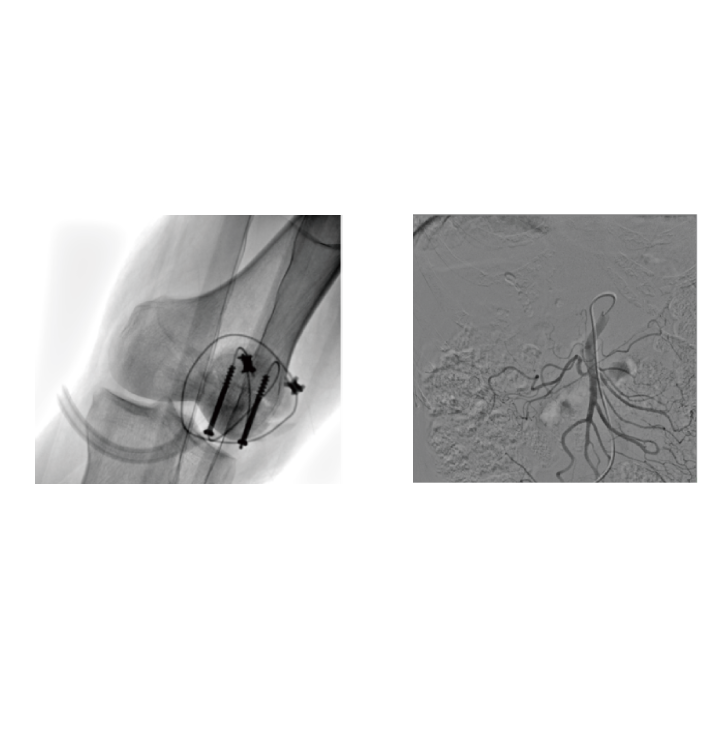

- Built-in three-dimensional tomography function, which can quickly reconstruct high-resolution stereoscopic images and assist in delicate operations such as pedicle screw placement and complex fracture reduction.

- From orthopedics and trauma surgery to peripheral intervention, it fully supports open surgery and minimally invasive intervention scenarios. One device meets diverse needs and helps hospitals optimize resource allocation.